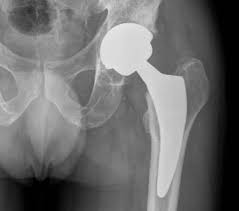

Protesi d’anca

È l’intervento sicuramente più comune e consiste nella sostituzione dell’articolazione con una protesi artificiale.

Vantaggi:

- Eliminazione del dolore

- Recupero della mobilità

- Miglioramento quindi della qualità della vita

Durata della protesi:

- In media 15–25 anni